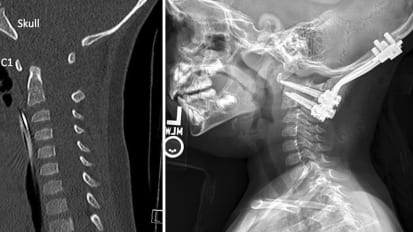

Lifesaving spinal fusion repairs toddler’s atlanto-occipital dislocation (AOD) News

Lifesaving spinal fusion repairs toddler’s atlanto-occipital dislocation (AOD)

Her two children were transported to Children’s Medical Center Dallas, a Level 1 trauma center where UT Southwestern pediatric neurosurgeon Bruno Braga, M.D., would not only save her son’s life but also give him a chance to once again become king of the playground.